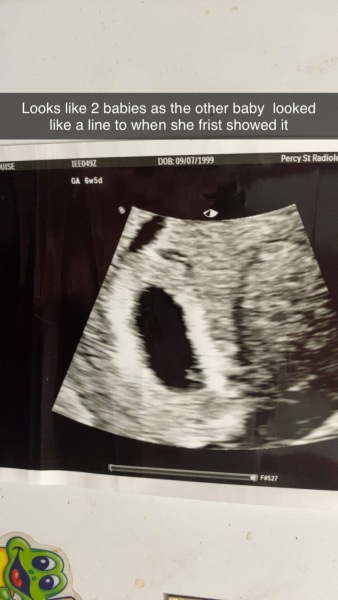

Is this twins I'm 7 weeks pregant

Idk I asked a lot of stuff and they said we can't tell u happend with all my kids but never on my other kids ultrasound have I had 2 sacks

Havnt said or told me anything hoptial does tho oh well just asking why I got 2 sacks in Bendigo it's different